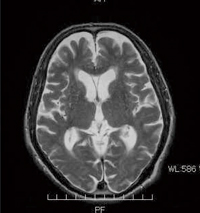

■症例2:頭部の短時間RADAR(体動低減法)

RADAR(パラレルイメージング併用)

頭部のT2WI,FSE,TR:4200,TE:91